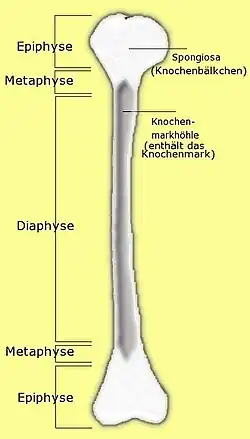

Der Oberarmschaftbruch, in der medizinischen Terminologie (Fachsprache) auch als Oberarmschaftfraktur, Humerusschaftfraktur oder diaphysäre Humerusfraktur bezeichnet, ist ein Bruch des Oberarmknochens (Humerus) im Bereich des Schaftes (Diaphyse), also außerhalb des Bereiches der angrenzenden Gelenke (Ellbogen- und Schultergelenk). Die Anatomie des Oberarmes, vor allem die enge Nachbarschaft zu Nerven (Nervus radialis) und Blutgefäßen, bedingt die besondere Problematik der Behandlung dieser Frakturen.